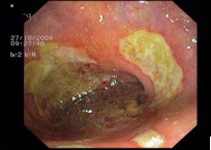

imagen3

Úlcera rectal múltiple